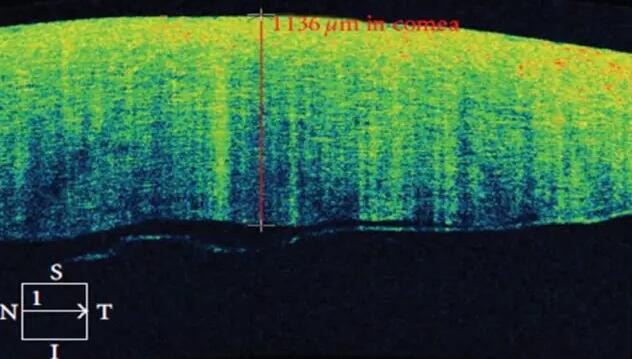

1、角膜分层观察 OCT 轴向分辨率高达5μm,远高于UBM(20--60μm),可识别出泪膜、上皮层、前弹力层、基质层、后弹力层/内皮层

2、角膜厚度评估,角膜水肿、瘢痕、混浊、溃疡、异物、炎症、胬肉等断层观察

3、角膜屈光手术后角膜瓣观察、角膜厚度评估等

4、后弹力层角膜内皮移植术(DSEK)、板层角膜移植术、白内障术后内皮层脱落等术后观察